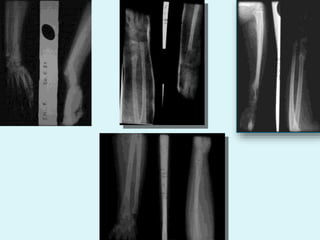

FRACTURE 2 OS AVANT BRAS

FRACTURE 2 OSAVANT BRAS